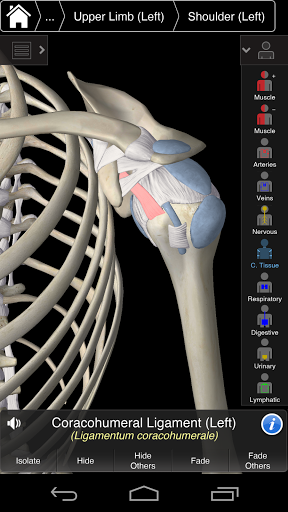

Essential Anatomy 3 reprezentuje najnowsze przełomowe technologie 3D i innowacyjny design. Najnowocześniejszy silnik graficzny 3D, zbudowany na zamówienie przez 3D4Medical od podstaw, zapewnia bardzo dokładny model anatomiczny i zapewnia doskonałą jakość grafiki, której żaden inny konkurent nie jest w stanie osiągnąć.

Aplikacja przedstawia unikalne podejście do uczenia się ogólnej anatomii. Grafika jest nieporównywalna i sprawia, że uczenie się, dzięki wykorzystaniu treści informacyjnej i innowacyjnych funkcji, jest bogatym i wciągającym doświadczeniem.

Essential Anatomy 3 jest responsywny, wizualnie oszałamiający i pozbawiony wysiłku. Aplikacja jest w pełni 3D, co oznacza, że możesz zobaczyć dowolną strukturę anatomiczną w izolacji, a także pod dowolnym kątem.

Mądra funkcjonalność znajdująca się w aplikacji pozwala użytkownikowi usunąć warstwy mięśni za pomocą narzędzia "skalpela". Ta aplikacja zapewnia użytkownikom możliwość włączania / wyłączania systemów bez potrzeby wyłączania poszczególnych struktur lub pomieszania wielu predefiniowanych kart regionalnych, tak jak w przypadku innych aplikacji.

Essential Anatomy 3 został zaprojektowany z myślą o użytkowniku - samo ciało staje się interfejsem. W odróżnieniu od innych aplikacji 3D, które opierają się na wcześniej zdefiniowanych układach anatomicznych i regionalnych rozbiorach, które kierują użytkownikiem, Essential Anatomy 3 3D4Medical pozwala znaleźć to, czego szukasz bez komplikacji.

---- Ponad 4000 bardzo szczegółowych struktur anatomicznych

---- nomenklatura łacińska dla każdej struktury anatomicznej